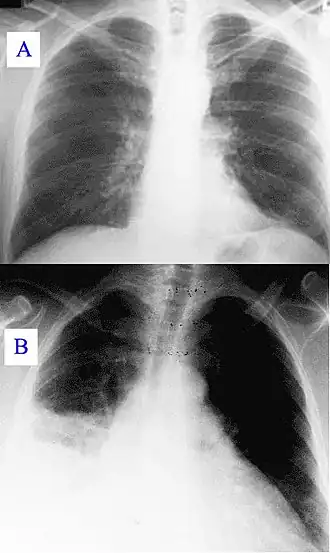

Durante el curso de la infección, la enfermedad puede progresar a una neumonía atípica, la cual puede desencadenar un síndrome de distres respiratorio agudo, tales síntomas usualmente ocurren durante los primeros 4-5 días de infección.

El diagnóstico se basa principalmente en los exámenes serológicos[6][7] para hallar anticuerpos en contra del antígeno bacteriano en lugar de buscarlo. La detección molecular de ADN bacteriano es cada vez más usada. El cultivo es técnicamente difícil y no está disponible de forma rutinaria en la mayoría de los laboratorios de microbiología. La fiebre Q puede causar endocarditis (infección de las válvulas del corazón) que puede requerir Ecocardiografía transesofágica para ser diagnosticada. La hepatitis de la fiebre Q se manifiesta como una elevación de la Alanina aminotransferasa y del Aspartato aminotransferasa, pero el diagnóstico definitivo sólo es posible con una biopsia hepática, que muestra los característicos granuloma en anillo de fibrina.[8]